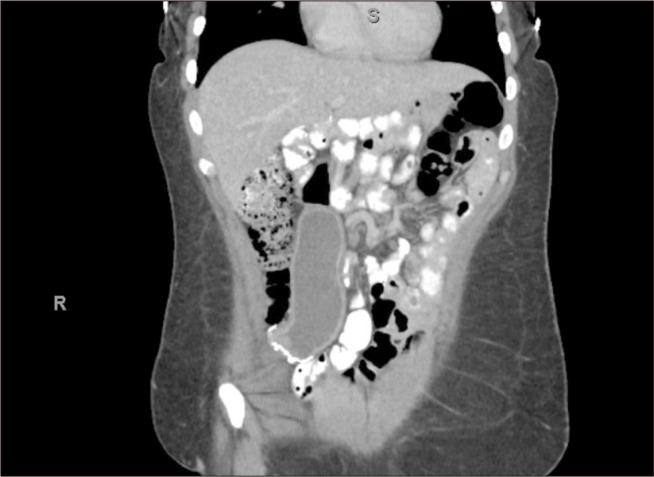

Gastric remnant volvulus following Roux-en-Y gastric bypass (RYGB) surgery is rare, with only two previously reported cases. Herein, we present the first case of gastric remnant volvulus following gastric sleeve conversion to RYGB in a 32-year-old female. Management for gastric remnant volvulus has not been clearly described in the literature due to the rarity of cases; however, previously documented cases of gastric remnant volvulus following RYGB were managed with gastropexy or resection of the gastric remnant. Due to anatomical limitations, gastropexy was not an option for our patient, and the remnant stomach was resected. Although management options are still evolving, surgical intervention is likely indicated for gastric remnant volvulus that develops following RYGB. To improve patient outcomes and establish more comprehensive guidelines for this uncommon condition, further studies on the management of post-RYGB gastric remnant volvulus are warranted since gastric sleeve conversion to RYGB is becoming more prominent.